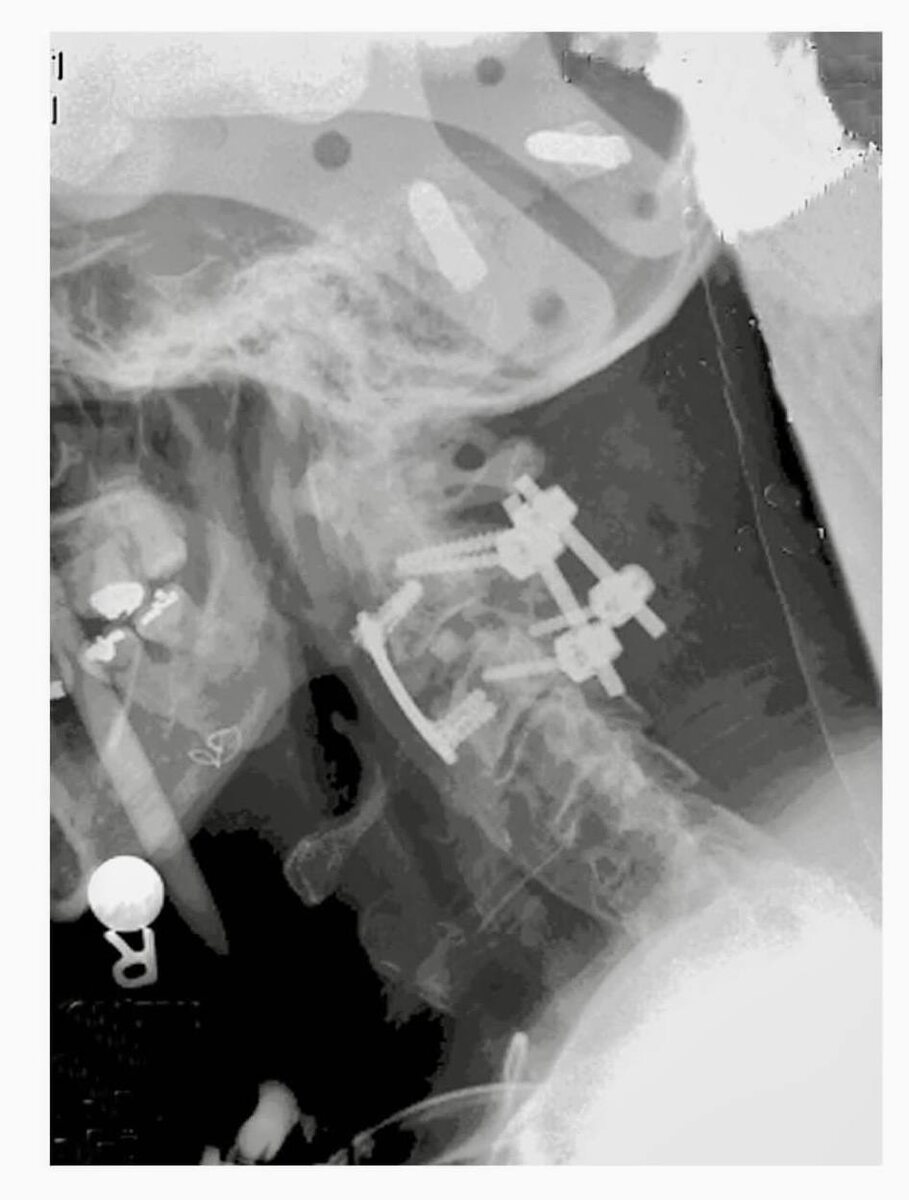

Пациентка 57 лет поступила после ДТП. Несмотря на крайне мерзкий первый снимок, выписалась без существенных неврологических нарушений (картинки из интернета)